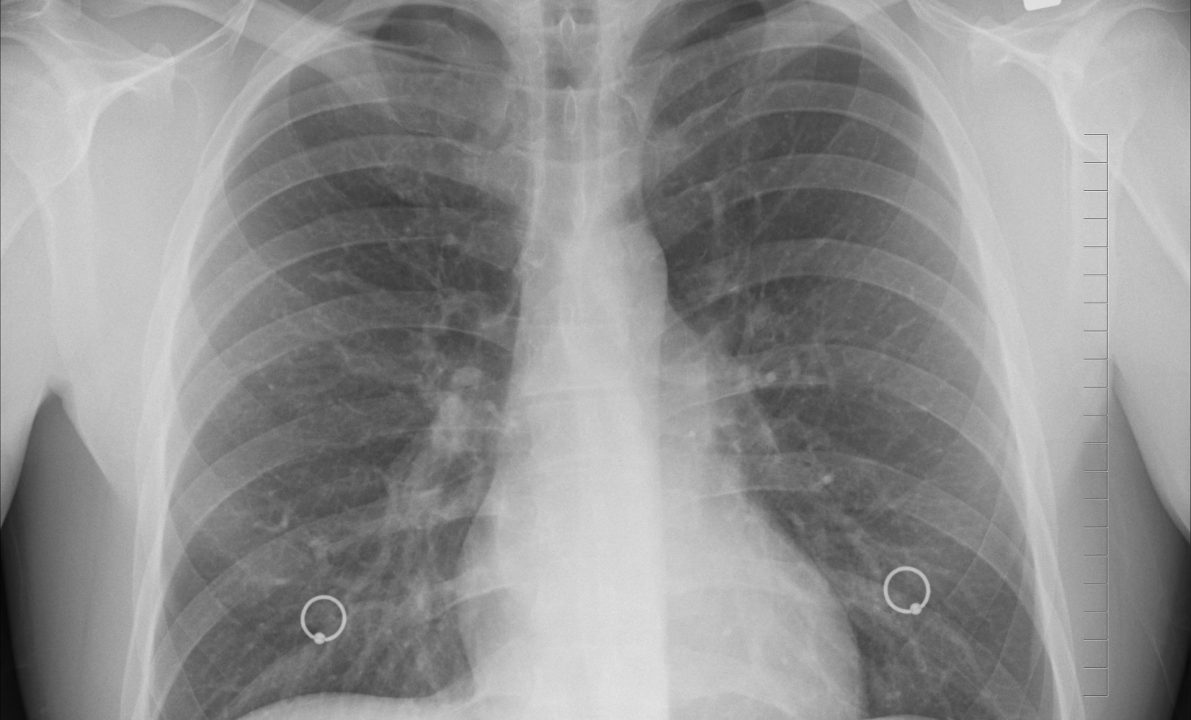

Una lastra al torace ha invece evidenziato una lesione nel lobo superiore destro dei suoi polmoni descritta dai sanitari come una “borsa rovesciata”. La 27enne è finita sotto i ferri e durante l’operazione i medici hanno fatto una scoperta choc. La donna aveva infatti un preservativo incastrato nei polmoni.